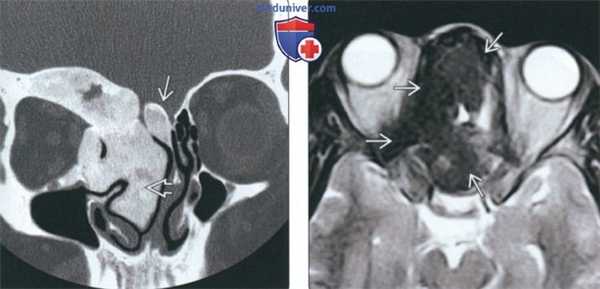

(Слева) При аксиальной «костной» КТ определяются классические признаки фиброзной дисплазии: выраженное вздутие левой верхнечелюстной пазухи с асимметричным выбуханием левой щеки, типичный вид «матового стекла». Обратите внимание на значительное уменьшение объема воздушной полости.

(Справа) При корональной костной КТ определяется фиброзная дисплазия с поражением правой нижней носовой раковины и латеральной стенки носа. Определяется выраженная экспансия раковины с изменениями в виде «матового стекла».

(Слева) При корональной «костной» КТ определяется экстенсивная фиброзная дисплазия орбит, петушиного гребня, решетчатой кости, среднего носового хода справа. Носовая перегородка отклонена влево.

(Справа) При аксиальной MPT Т2 в зоне фиброзной дисплазии определяется характерный выраженный гипоинтенсивный сигнал. Эти изменения типичны, когда наблюдаются совместно с «матовым стеклом» на КТ, и более диагностически значимы, чем гиперинтенсивные на Т2 очаги.